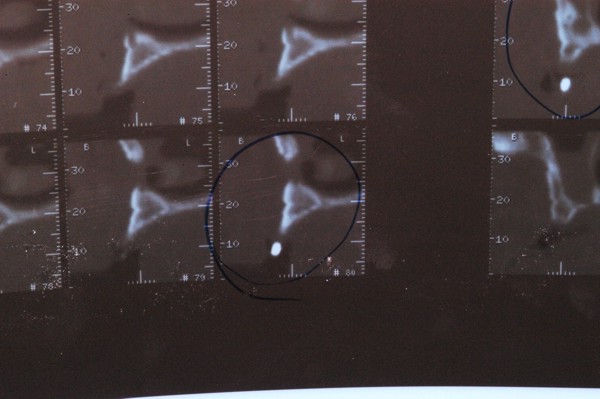

ABSTRACT La literatura oclusal se ha encargado de describir distintas funciones de la misma a través de los tiempos. El presente caso se realiza en forma de sobredentadura (over denture) debido a que la carencia de reborde óseo en el sector anterior verificado tanto clínicamente como mediante telerradiografía , impedía llevar a cabo una prótesis fija , por lo que se optó por un sistema de pilares ceramizados y paralelizados mediante el sistema SIRIUS, sobre seis implantes, y la conexión a una estructura de metal cerámica FIJA AMOVIBLE, mediante coronas telescópicas galvanizadas, otorgando al sistema la rehabilitación mediante una PIA(Prótesis Implanto Asistida con reposición ósea y gingival mediante porcelana rosa.) MATERIAL Y MÉTODOS: IMPLANTES:KLOCKNER SK-T.T.S. MONTAJE Y REGISTROS: ARCO FACIAL ESTÁTICO Y ARTICULADOR PRIMARIA: Abuttmets Ceramizados (I.P.S. D.SIGN IVOCLAR) SECUNDARIA: Cofias Galvanoformadas (AURO GALVAN CROWN WIELAND) TERCIARIA: Férula de Porcelana sobre Metal (I.P.S. D. SIGN IVOCLAR) CEMENTADO INTERFASE: NIMETIC CEM-ESPE DESARROLLO Se presenta el paciente a la consulta requiriendo la resolución de su maxilar inferior, el que se restaura mediante una férula de metal porcelana , en la que se preparan los lineamientos oclusales ideales (Spee-Wilson-Cuatro Niveles-etc) a fin de tener un sustrato de trabajo correcto, para la confección del maxilar superior, que porta una Prótesis Total convencional. Se estudia mediante Panorámica, Dentascan y Montaje en articulador semi ajustable. Se instalan seis implantes Klockner con Técnica Semisumergida pensados para una Carga diferida a tres meses después de la implantación Se realiza el arrastre de los Transfer mediante cubeta individualizada y fenestrada. Se confeccionan los abuttmentes correspondientes y se llevan a boca mediante una férula de posicionamiento realizada en Acrílico Duralay, el que por sus condiciones de carencia de cambios volumétricos verifican el correcto ajuste de los mismos Se ceramizan los abuttments y se paralelizan mediante el sistema SIRIUS, llevándolos a boca y chequeando su instalación Se confecciona una Prótesis Total Provisional que llevará el paciente durante el período de Osteointegración Se procede a la confección en laboratorio de las cofias galvánicas Sobre un nuevo modelo mayor se confecciona la férula de metal que uniremos en boca a las cofias galvanizadas mediante un cemento especial, una vez confeccionada la porcelana. Se prueba en boca la férula metálica, verificando su holgura que será ocupada por el cemento antedicho, y se comienza con el montaje de la cerámica y la verificación de los patrones oclusales de la misma. Se instala el todo haciendo morder al paciente con el medio cementante instalado. FIGURA 40 FIGURA 41 FIGURA 42 CONCLUSIONES La función de «GUIA CANINA», como esquema mas propicio para cumplir con los deseos de «autoprotección » de un SEG, rehabilitado o no, no se cumple al 100 % en casos como el presentado. La razones por las cuales el uso de la misma en lo que se da en denominar OCLUSIÓN MUTUAMENTE PROTEGIDA consiste en tres factores que detallo a continuación: A. En una función desoclusiva realizada por las piezas anteriores, como por ejemplo el canino, el BRAZO DE RESISTENCIA generado en la palanca desoclusiva, es por lo menos igual al brazo de potencia desarrollado, argumento de gran peso para hablar de la Desoclusión Canina como esquema de elección- B. La inclinación de los rebordes marginales del canino superior, esta dentro de los 70º, a diferencia de la tabla oclusal posterior que puede variar entre los 20 y 40 º. C. El estimulo que generan los dientes anteriores se dirige por via aferente al SNC, exitando por vía eferente, fundamentalmente al músculo temporal en sus fibras anteriores o VERTICALES…fibras de mucha menos capacidad de fuerza, que si la acción la ejercieran las fibras de la cincha PTERIGO MASETERINA, que serían exitadas en el caso de una Función de Grupo. EN EL CASO PRESENTADO LAS DOS PRIMERAS RAZONES TIENEN VIGENCIA. Sin embargo la última de ellas , al no tener los Implantes terminaciones nerviosas como las que posee el periodonto , los estímulos que llegan al SNC no se cumplen, y por lo tanto no existe la respuesta que por conducción eferente estimularía al músculo temporal a su acción. De la misma manera, el hecho que estos Implantes estén ferulizados , trasmite fuerzas laterales también a los posteriores, y no solo a los que actúan como caninos. El beneficio de las dos primeras razones de uso de una Función Canina en un caso como este, obedece a que de por si las mismas minimizan la acción direccional de las fuerzas, las que sin embargo son compartidas por las piezas posteriores tanto del LT como del LnT. En este compartir de la función, me resulta conveniente denominar a este esquema: FUNCIÓN DE GRUPO POSTERIOR DE ACCIÓN CANINA. ———————————————————————————————————- PIE DE FOTOS: 37: CASO TERMINADO